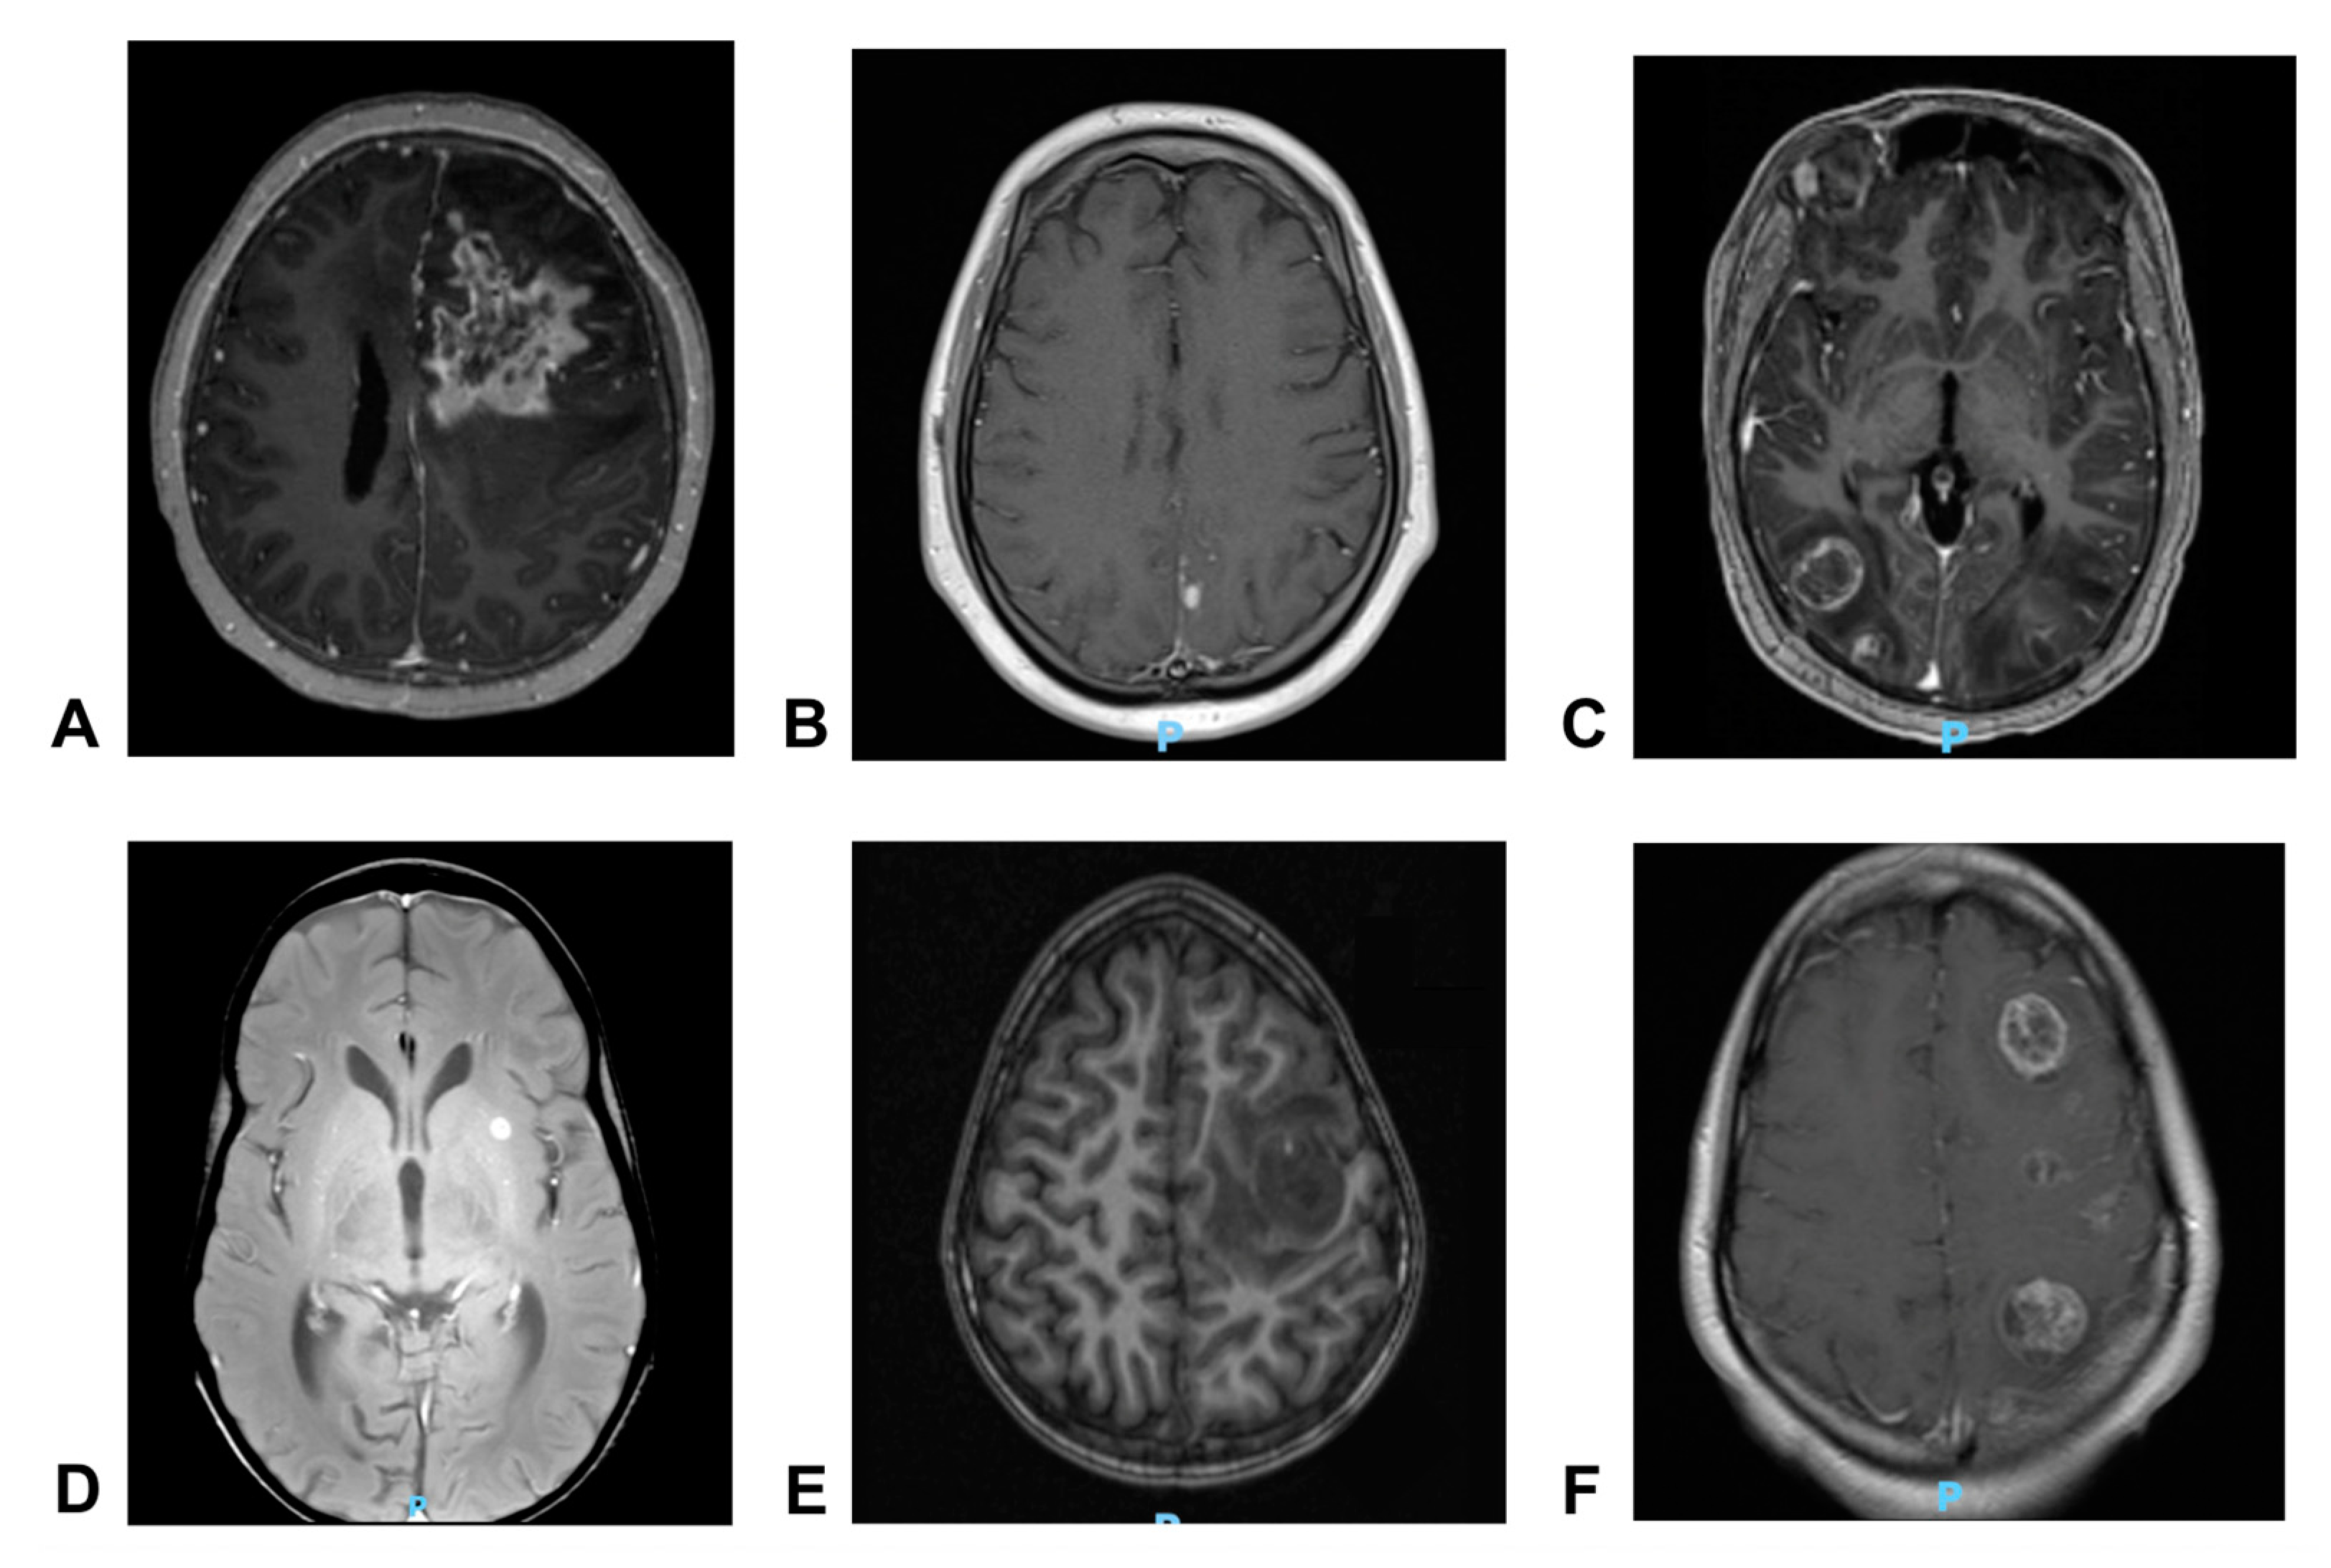

3.1. Patient #1

3.2. Patient #2

3.3. Patient #3

3.4. Patient #4

3.5. Patient #5

3.6. Patient #6